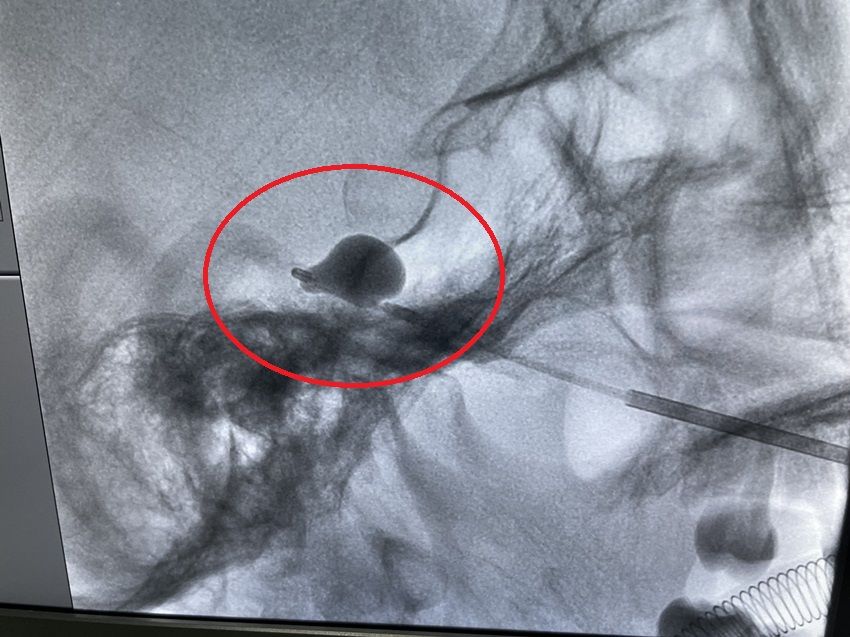

文章插图

▲调整位好位置后置入一次性球囊导管,将造影剂注入球囊中

文章插图

▲待球囊扩张呈梨形后,予球囊压迫3分钟。解除球囊压迫,退出球囊导管及穿刺针,手术结束。